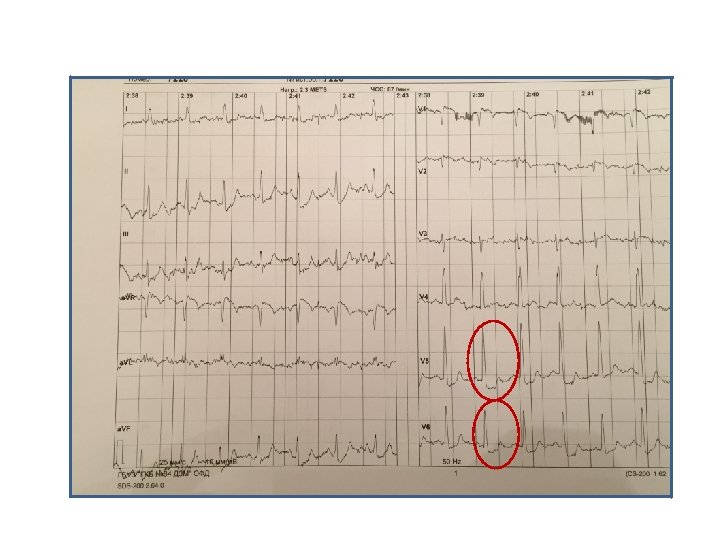

Пациент Б. , 58 лет Направление: диагностика ИБС

Пациент Б. , 58 лет Направление: диагностика ИБС